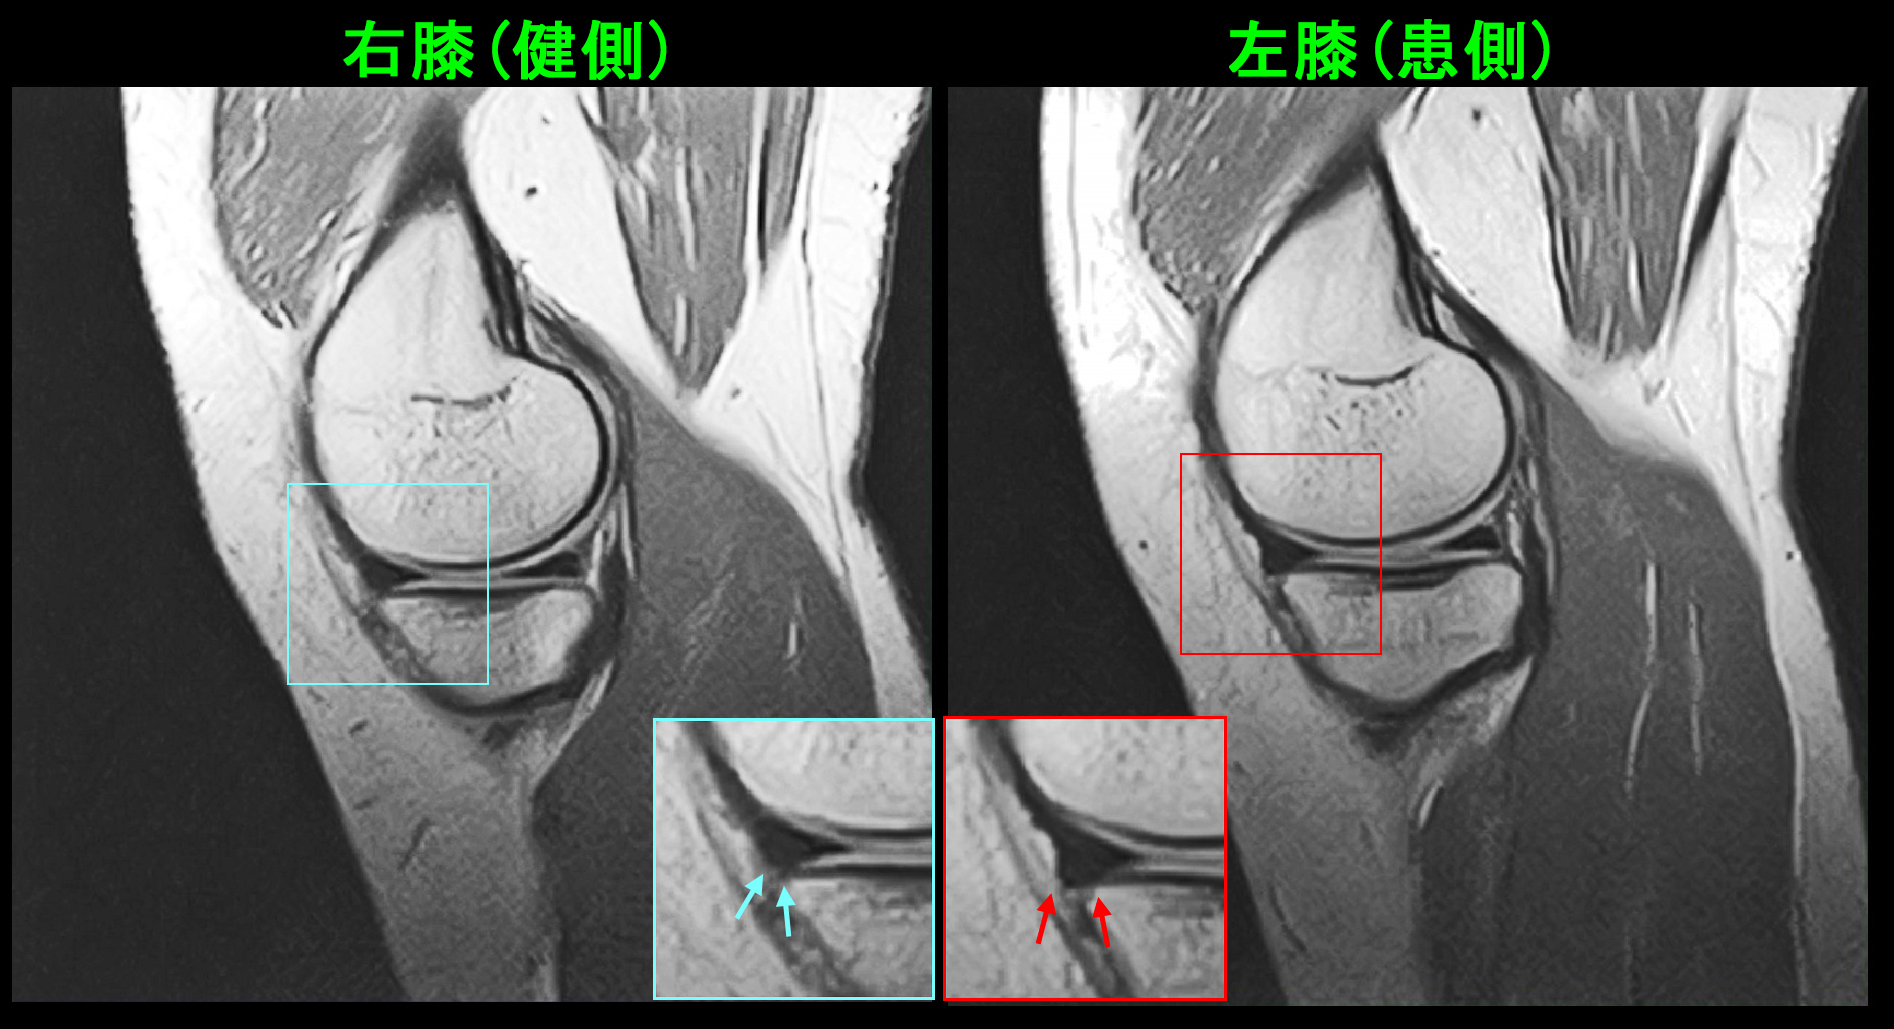

18才女 MR1.jpg

MR所見で左脛骨の骨には異常はありませんでしたが、PDの冠状断(前からみた画像)では左の内側半月板は右に比して膨らんでいる印象です。